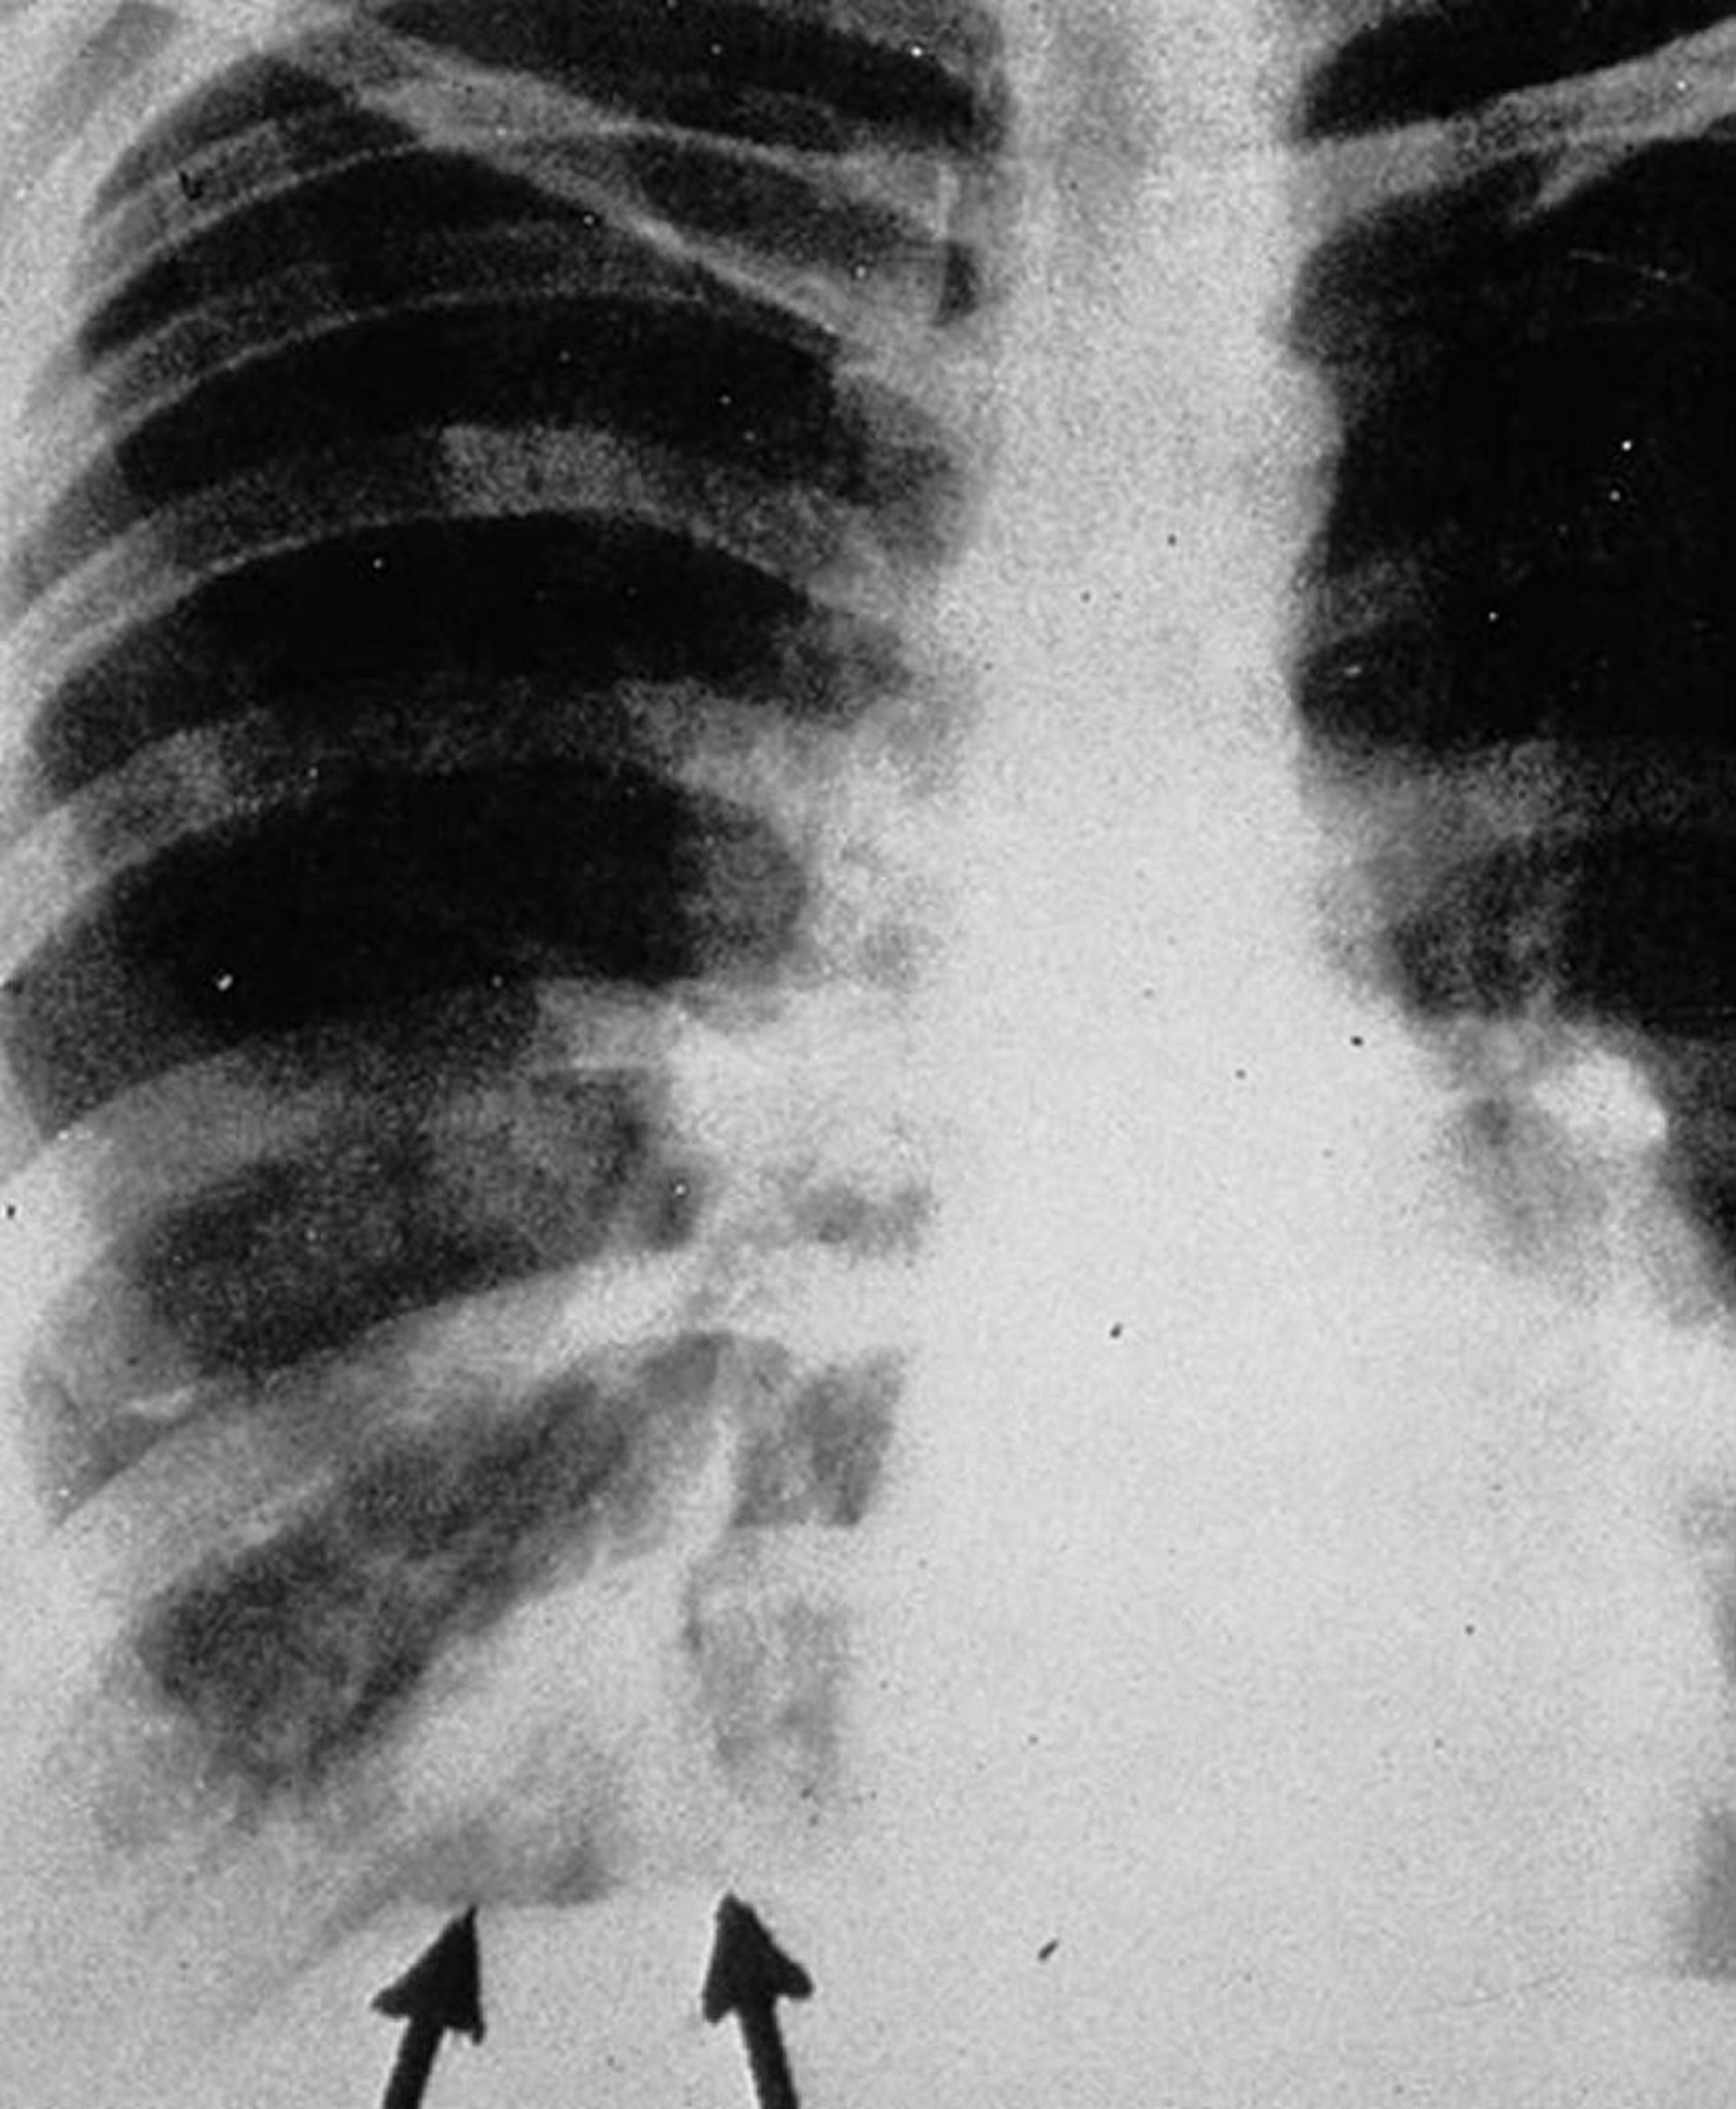

Аллергический бронхолегочный аспергиллез

На заднепередней рентгенограмме грудной клетки видны затенения по типу «пальцы в перчатке» (показано стрелками), которые проявляются в виде разветвленных тубулярных уплотнений, представляющих собой экссудат, образующийся внутри бронхов, с утолщением бронхиальных стенок.